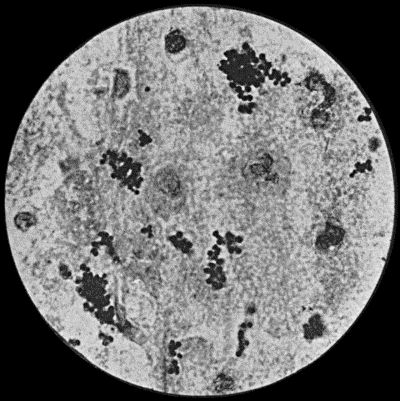

Fig. 3.—Streptococci in Pus from an acute abscess in subcutaneous tissue. × 1000 diam. Gram's stain.

Streptococcus Pyogenes.—This organism also varies greatly in its virulence; in some instances—for example in erysipelas—it causes a sharp attack of acute spreading inflammation, which soon subsides without showing any tendency to end in suppuration; under other conditions it gives rise to a generalised infection which rapidly proves fatal. The streptococcus has less capacity of liquefying the tissues than the staphylococcus, so that pus formation takes place more slowly. At the same time its products are very potent in destroying the tissues in their vicinity, and so interfering with the exudation of leucocytes which would otherwise exercise their protective influence. Streptococci invade the lymph spaces, and are associated with acute spreading conditions such as phlegmonous or erysipelatous inflammations and suppurations, lymphangitis and suppuration in lymph glands, and inflammation of serous and synovial membranes, also with a form of pneumonia which is prone to follow on severe operations in the mouth and throat. Streptococci are also concerned in the production of spreading gangrene and pyæmia.

Division takes place in one axis, so that chains of varying length are formed (Fig. 3). It is less easily cultivated by artificial media than the staphylococcus; it forms a whitish growth.